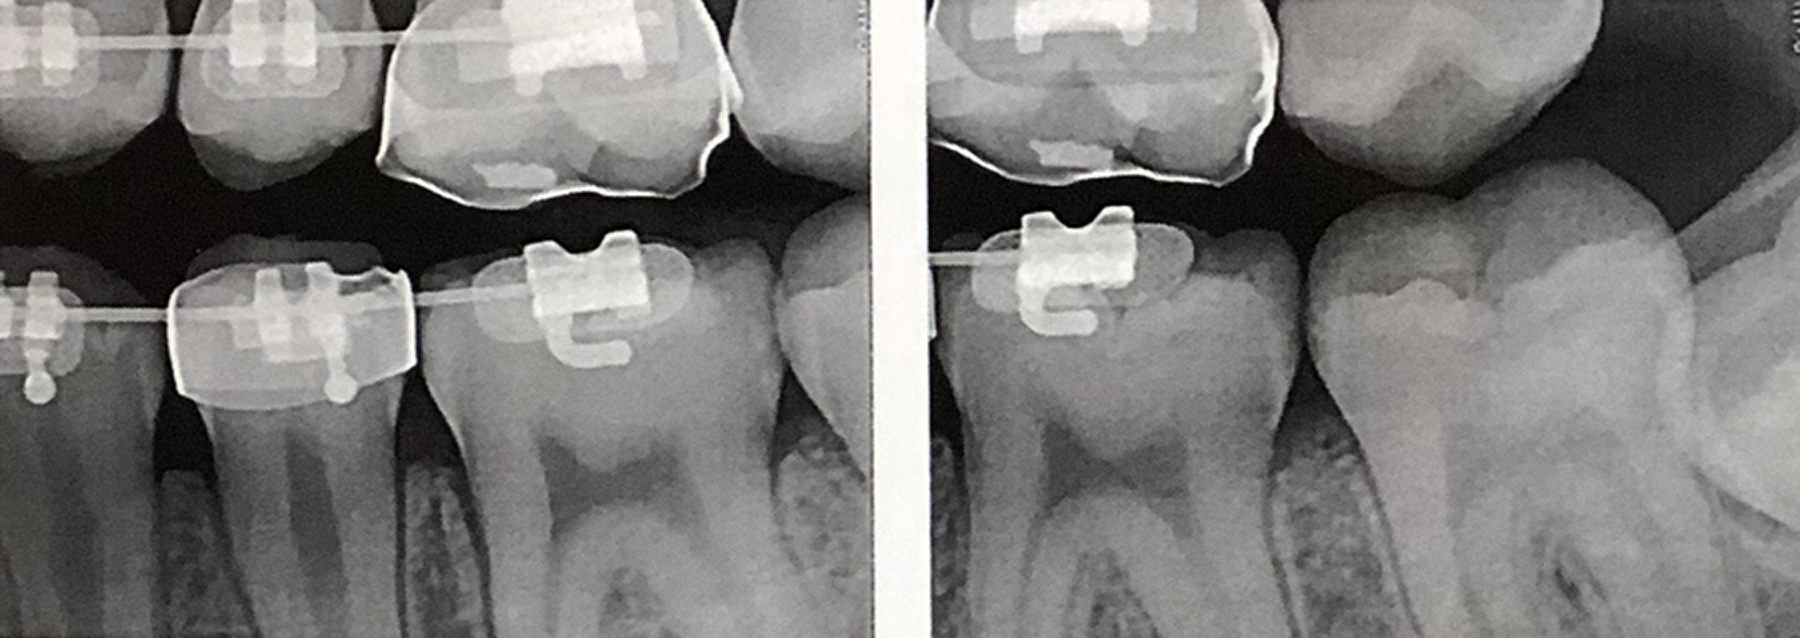

(18.) Radiograph of teenage patient showing maxillary left first premolar, which will be scheduled for disto-occlusal restoration, and all other proximal sites that will be treated with dental pick applied SDF. Additional application of SDF planned for 3 months and new bitewing films to be recorded in 6 months.

Figure 18